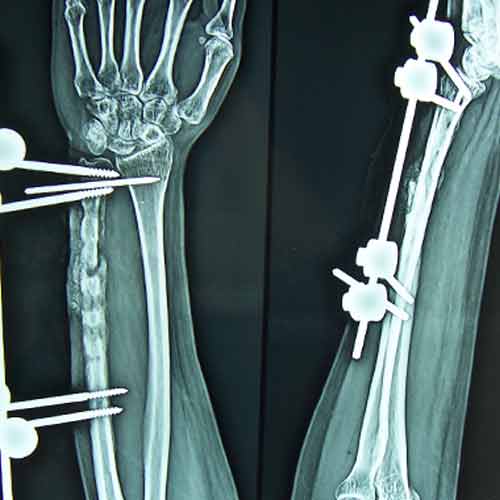

31 years old patient with fracture radius-ulna (1-year-old) with infected non-union was treated with implant removal & external fixation. ‘K’ wiring was done for distal radio-ulna joint stabilization. Bone grafting was done after 3 weeks. Fracture united 6 months’ post-operative.

Pre-Op

Post-op

Imm Post-op

Bone gratfing + ex fix

6 months post-op